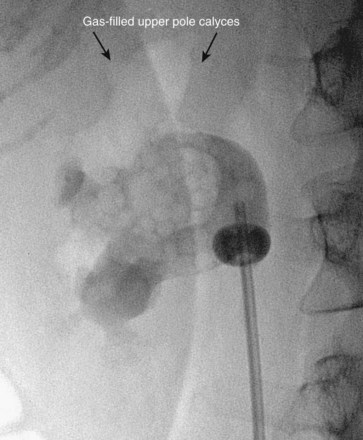

Figure 47–18 Injection of air into contrast-filled upper tract collecting system reveals posterior calyces, in this case most clearly the upper pole calyces. Compare with Figure 47–12, before injection of air.

There are two well-described methods of fluoroscopic guidance for antegrade percutaneous access into the upper urinary tract collecting system: the “eye-of-the-needle” technique and the “triangulation” technique (Miller et al, 2007). Both have their proponents, and there is no clear advantage of one over the other. Through the retrograde device, inject contrast material to delineate the collecting system after first taking note of any radiopaque pathology for later reference. Comparing a spot film of the unopacified collecting system with the opacified view is useful in this regard. Once the options for the calyces of entry are identified, inject air to define which calyces are posterior. In the prone position, air rises up the posterior calyces. The “double-contrast” pyelogram (both contrast material and air) provides the best determination of the pertinent intrarenal anatomy.